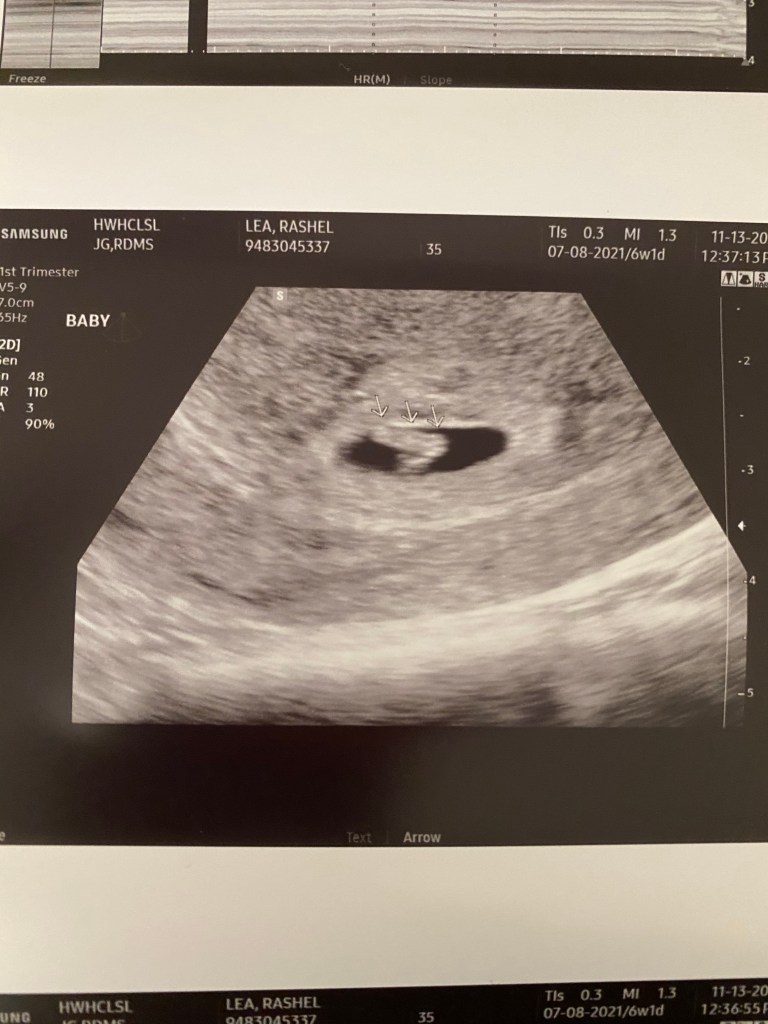

At first I was worried I could see the blob of the baby but I couldn’t see the flickering of the heartbeat. She assured me it was there and she could see it. She zoomed in and then I could too!! 😍 I immediately felt so so much better and calm. Then I was on the hunt making sure I only saw the one little guy. Good news for me it looks like it’s one strong little guy growing in there. I’m so relieved and happy for all of us.

The ultrasound technician said baby looks perfect and is measuring at 6 weeks and 4 days so a little bigger then we’re we are. I should be 6 weeks one day since we know the exact moment he went in 😂. His heart rate is a solid 114 so that’s great too. So much joy and happiness today.